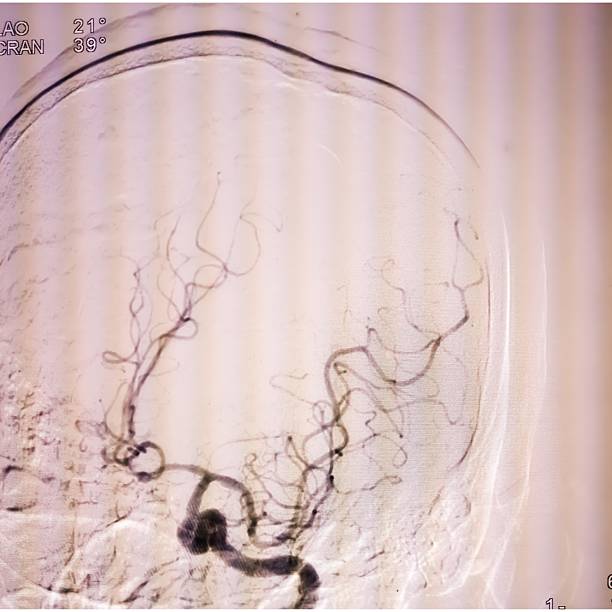

뇌경색은 뇌혈관이 막히면서 해당 부위에 혈액이 공급되지 않아 뇌세포가 손상되는 질환이에요.

**‘허혈성 뇌졸중’**이라고도 하며, 전체 뇌졸중의 약 **70~80%**를 차지할 만큼 흔한 형태입니다.

보통은 고혈압, 당뇨, 고지혈증, 흡연, 심장질환 등이 주요 원인으로 작용하죠.